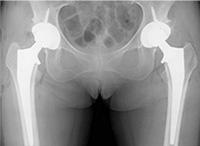

手术后X线图像

关节软骨磨损,关节的缝隙变窄,白色部分为人工关节。